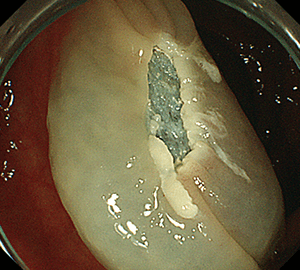

コールドスネアポリペクトミー(CSP)

当院の院長もその発展と普及に尽力してきた、高い安全性と有効性を両立した治療法です。

合併症の非常に少ない優れた治療法であることから、近年大腸ポリープの外来切除法として急速に施行件数が増えてきています。当院ではこのコールドスネアポリペクトミーを主体としたポリープ切除を行っています。

1:ポリープを見つけます。1:ポリープを見つけます。

2:NBI併用拡大観察で詳細に観察します。2:NBI併用拡大観察で詳細に観察します。

3:病変をスネアに通します。3:病変をスネアに通します。

4:周囲の正常粘膜をしっかり入れながら、病変を絞扼していき…4:周囲の正常粘膜をしっかり入れながら、病変を絞扼していき…

5:切除します。切除検体は吸引回収し、病理検査を行います5:切除します。切除検体は吸引回収し、病理検査を行います。

6:切除後に洗浄・観察して、病変の遺残がないことを確認します。6:切除後に洗浄・観察して、病変の遺残がないことを確認します。